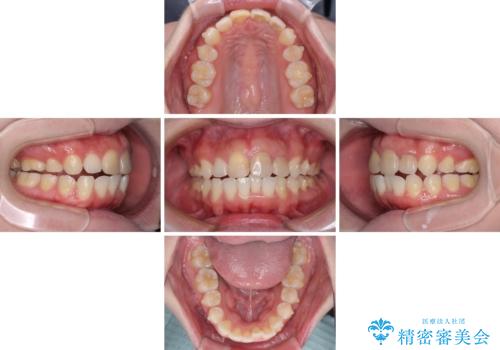

抜歯矯正の後戻り インビザラインによるオープンバイトの再矯正

上下前歯のオープンバイトを改善するため、インビザラインにて治療を行うこととしました。

外食が楽しみである患者様だったので、インビザラインによる治療期間は我慢の時期であったようです。

自己管理を徹底していただいたので、1年程度で治療を終えることができました。